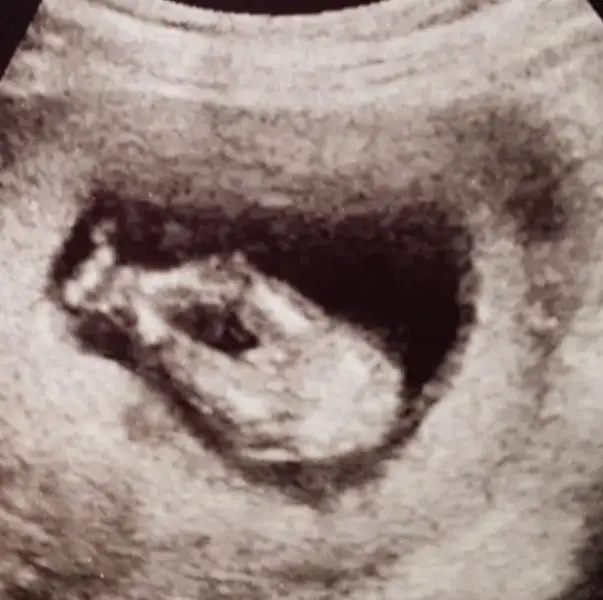

Ben hiç anlamam canım fotodanAy insallah canim Allah razi olsun:) erken soyleyip rezik olmaktan korkuyoruz ama doktor yuzde yuz dedi tum acikligi ile gosterdi ama icimde hala endise var. Herks duydu. Af dileyerek bi foto koysam birde siz baksanizEki Görüntüle 2097244

Canim bana da erkek gibi geldi. Hem rezil oluruz diye dusunme rezil olcak ne var. Komik bi ani olarak kalir.Ay insallah canim Allah razi olsun:) erken soyleyip rezik olmaktan korkuyoruz ama doktor yuzde yuz dedi tum acikligi ile gosterdi ama icimde hala endise var. Herks duydu. Af dileyerek bi foto koysam birde siz baksaniz